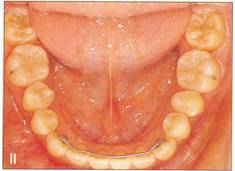

Fi 545e45f g S.8a Preoperative panoramic view. The maxillary left first premolar will be extracted for orthodontic reasons and transplanted to the area of mandibular left second premolar in a 15year-old female. Fi 545e45f gs S-8b to 5-89 Preoperative intraoral view. Fi 545e45f g S-8h Preoperative view. |